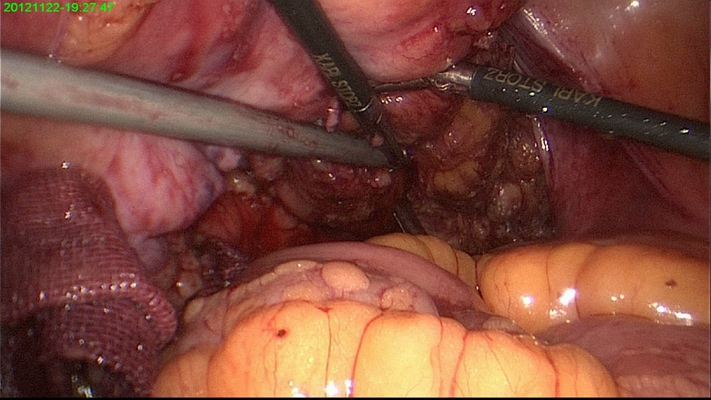

直腸癌圖片

直腸癌晚期症狀 (5)